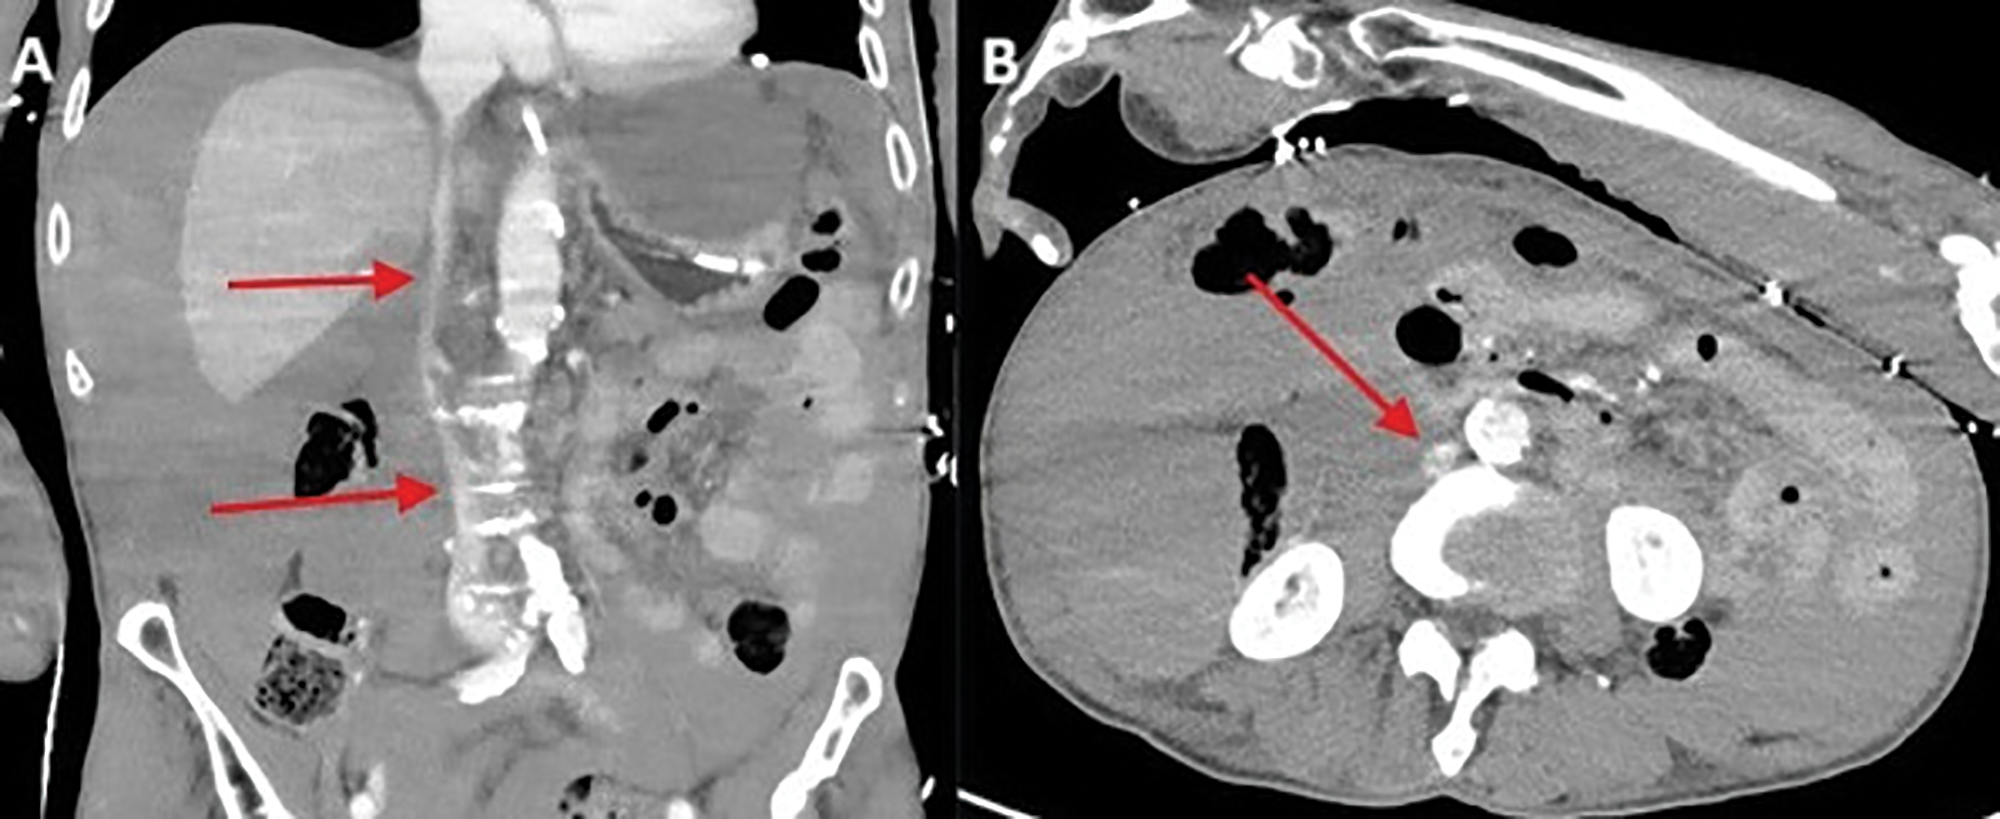

Figure 3

Gracile appearance of the inferior vena cava and the major pelvic veins.